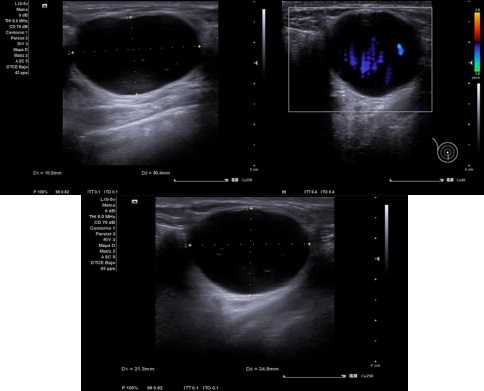

Caso 1: Mujer de 45 años con bulto doloroso en mama derecha, descubierto hace un dia, MD tumoración de unos 3 cm, móvil, bien delimitada, no adherida a planos profundos.

Caso 1: Imagen anecoica de 25 x 30 x 25, que deja refuerzo posterior, sin captar doppler compatible con Quiste mamario.

Caso 1: Quiste mamario.

Diagnóstico diferencial: Fibroadenoma de mama.